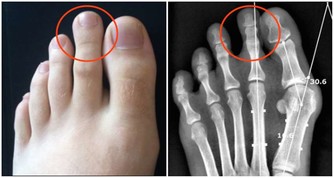

以下圖片來源 西醫認為: 缺鈣和脊椎的形變是最大的禍首。如果不及時治療,那麼,隨著鈣質的繼續流失、包括頸椎和腰椎兩大人體主要部位的形變,隨之而來的由骨折引起的死亡,腰椎、頸椎引起的腦供血不足和癱瘓等等,也會慢慢接近。